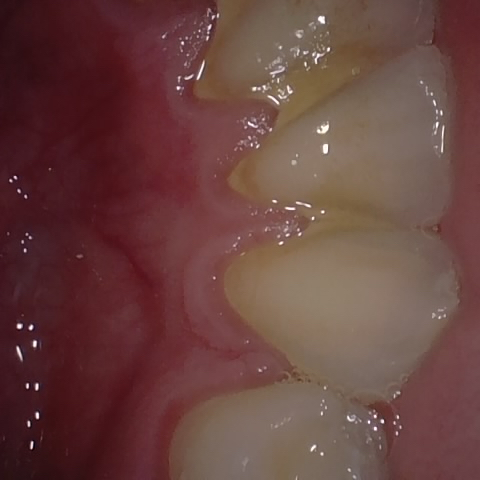

Annotated as "Good"